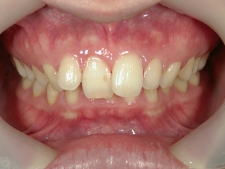

アクアシステム(透明マウスピース矯正)/上顎のみ 症例(1)

28歳 女性 浜松市中区在住  治療期間1年4ヶ月

矯正歯科 治療前

矯正歯科 治療前 正面